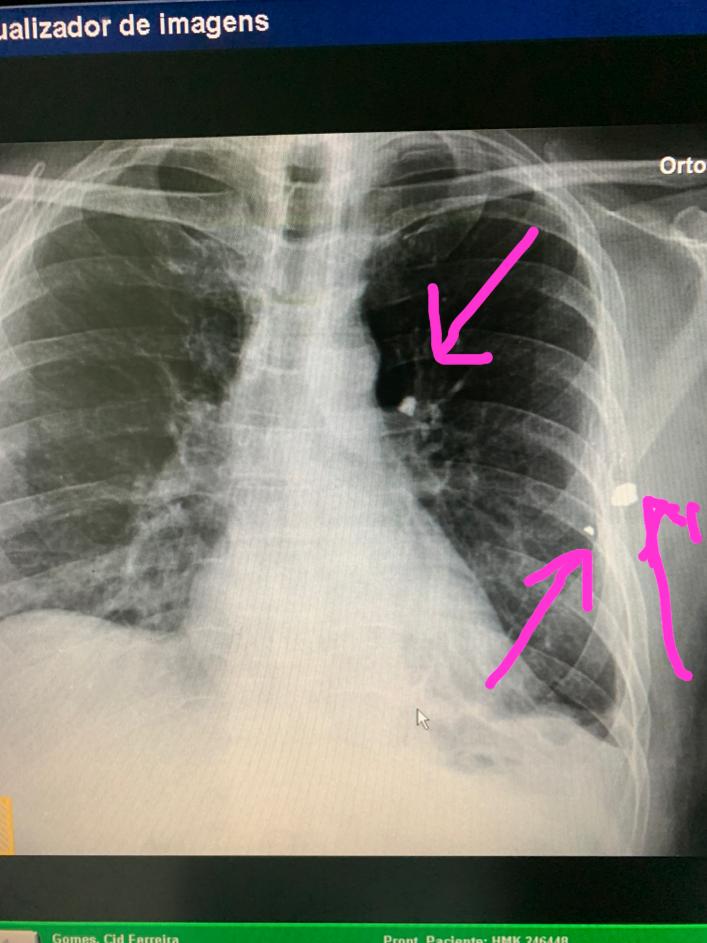

A alta médica era aguardada para o final da tarde de sábado, 22, mas a equipe médica liderada pelo Dr. Cabeto optou por mais alguns exames – entre eles, um raio-x confirmando que há dois projéteis alojados, um ao lado da costela e outro no pulmão esquerdo, assim como fragmentos de projétil – antes de definir que não será feito procedimento para a retirada das balas alojadas.

- Raio X Tórax